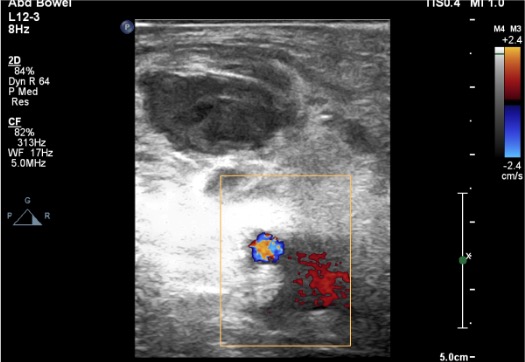

- Evaluate for AV fistula component (critical — thrombin ineffective if AVF present)

Concomitant Arteriovenous Fistula Detected

Thrombin injection is ineffective if a significant AV fistula is present (continuous high-velocity flow prevents thrombosis). Requires concomitant coil embolization of the fistulous tract, covered stent, or surgical repair. Always evaluate for AVF on duplex US before proceeding with thrombin injection.